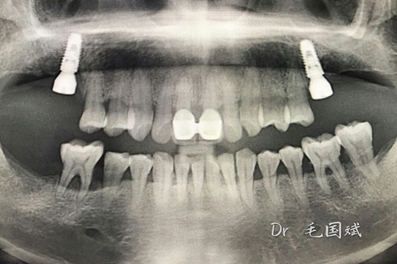

毛國(guó)斌種植病例——群討論分享